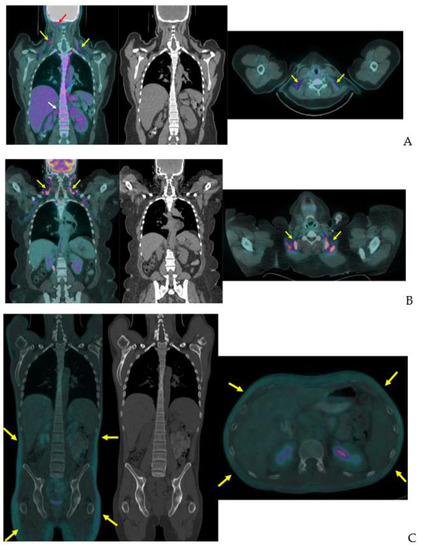

Prospective studies often use cooling protocols to induce iBAT activation. Leitner and colleagues showed a 20 min cold exposure is sufficient to activate iBAT in healthy adult volunteers [58]. In their study, 3 h of rewarming after cold exposure decreased FDG uptake by iBAT to near baseline [58]. Indeed, iBAT is so temperature sensitive a NIH expert panel recommends reporting outdoor temperature, season, and geographic location in any FDG-PET/CT study of iBAT [13]. Despite the strong association with cooler temperatures, we routinely see active iBAT on warm days in our large oncology practice where the uptake room is held at a constant temperature warm enough to prevent shivering. Figure 6 shows examples of the wide variation of uptake in clinical patients.

Figure 6.

Variation of BAT FDG uptake in clinical patients. Fused coronal FDG-PET/CT, coronal CT, and fused axial FDG-PET/CT (A–C). (A) BAT FDG uptake in a woman with normal BMI. Note supraclavicular (yellow arrows), skull base (red arrow), paraesophageal (blue arrow), and perinephric (white arrow) uptake. (B) Supraclavicular BAT in an obese woman (yellow arrows). (C) Diffuse FDG uptake in subcutaneous WAT in a male patient (yellow arrows). (D) A male patient with extensive supraclavicular FDG uptake extending into the upper neck (yellow arrows) and paravertebral BAT activity (blue arrows).